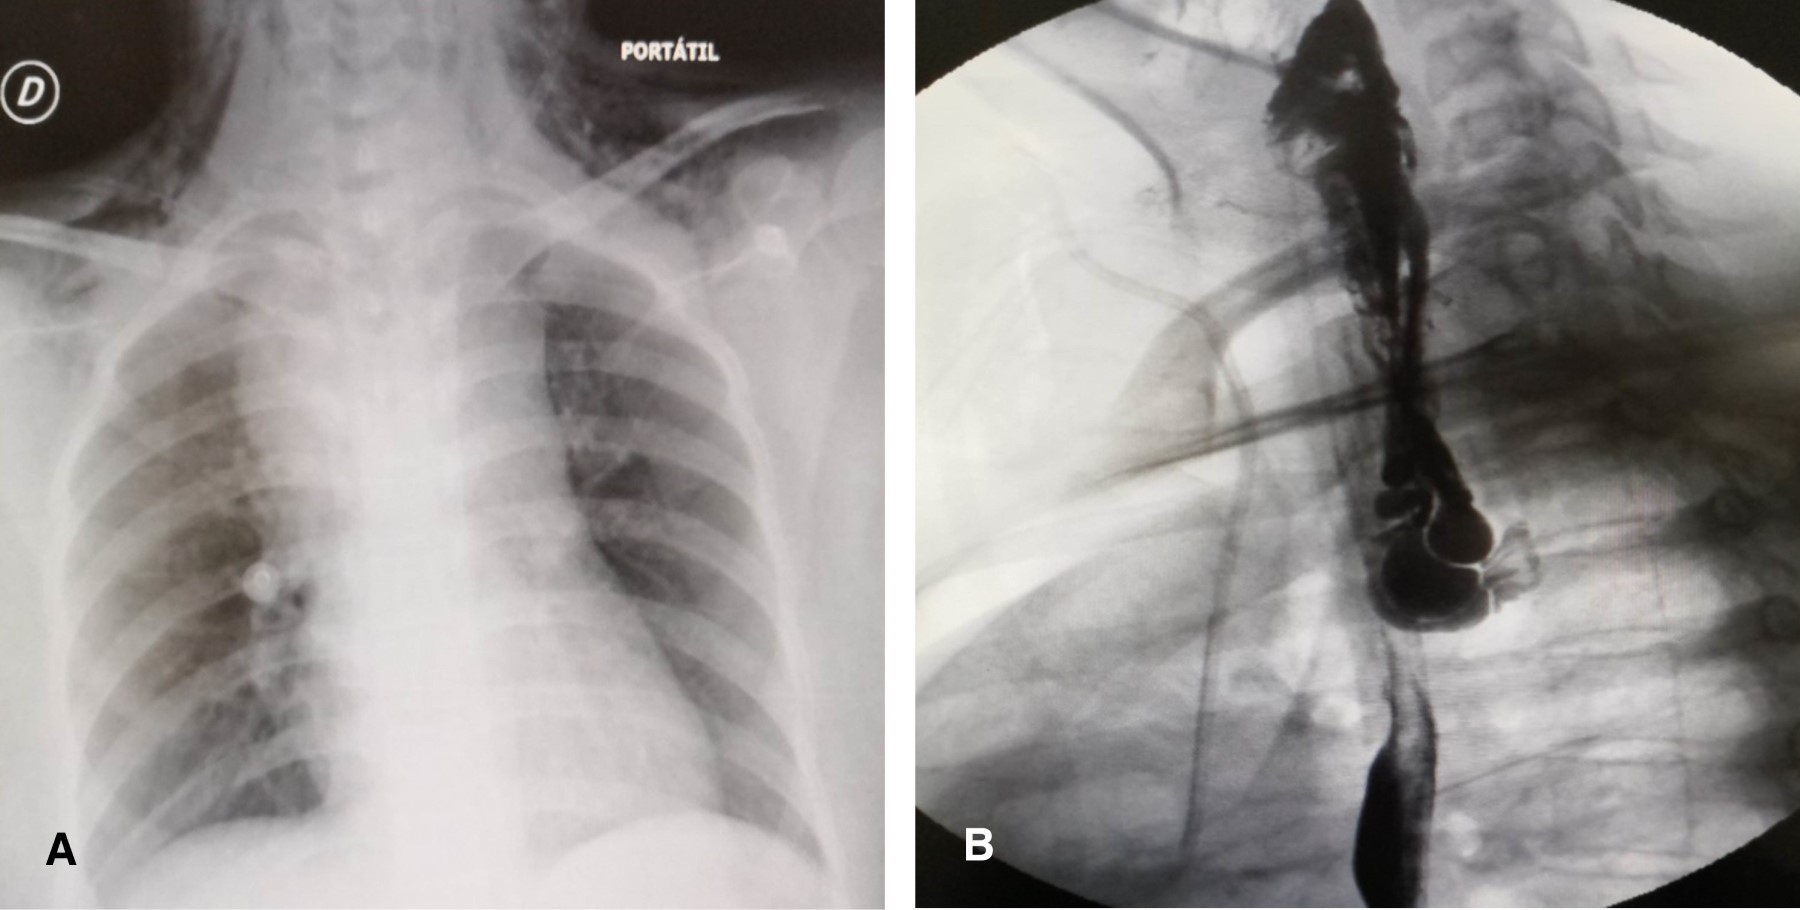

Paciente femenino de 16 años que inicia con vómitos y evacuaciones diarreicas secundario a gastroenteritis infecciosa, más tarde con aumento de volumen y dolor en región cervical izquierda, acudió al servicio de urgencias con disfagia, fiebre y enfisema subcutáneo cervical y torácico superior. En la radiografía cervicotorácica se identificaron enfisema subcutáneo, ensanchamiento mediastinal y neumomediastino. Una serie esofagogastroduodenal documenta fuga de material de contraste a nivel del esófago superior con extensión a mediastino con impresión diagnóstica de perforación esofágica cervical izquierda espontánea con compromiso mediastinal (Figura 1).

En las perforaciones cervicales el dolor puede estar acompañado de tumefacción e hipersensibilidad del músculo esternocleidomastoideo;15 un diagnóstico tardío de más de 24 horas posterior a la perforación está asociado a un incremento de la morbilidad y mortalidad.14,16 El diagnóstico temprano requiere un alto índice de sospecha, en el cual el enfisema es corroborado por la radiología simple y la evaluación tomográfica del cuello y tórax, como en nuestro reporte un trago de medio de contraste hidrosoluble confirma el diagnóstico y define el sitio exacto de la perforación.16,17 Aunque las complicaciones respiratorias e intratorácicas no son frecuentes en la perforación faringoesofágica (10% con respecto a las perforaciones esofágicas torácicas de 50%), el ensanchamiento mediastinal y el enfisema subcutáneo de la radiología simple de cuello y tórax permitieron identificar y diseñar el algoritmo terapéutico del absceso mediastinal detectado por la tomografía.17 Las anteriores consideraciones asociadas al sitio de perforación en la pared lateral de la hipofaringe podrían obedecer a un incremento súbito de la presión en la orofaringe e hipofaringe como resultado de una incoordinación neuromuscular y falla en el mecanismo de relajación del músculo cricofaríngeo, y explicar esta predisposición a la perforación faringoesofágica espontánea de nuestra paciente y de otros reportes previamente descritos.12,18-21